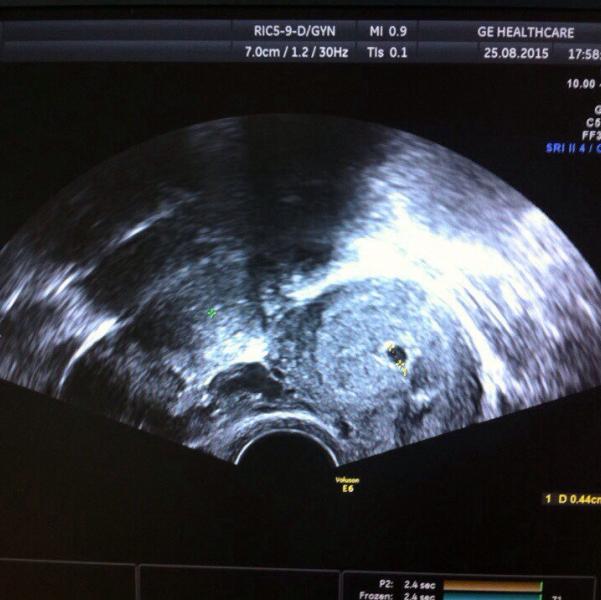

8-ого апреля утром просыпаюсь, девчонки смеются, типа думали Наташу назад вернули, не родила (это роженица, которую до меня забрали рожать, а меня на ее место положили). Потом с девчонками позавтракали. У меня ни ложки, ни стакана не было (вот думаю ппц собрали они мне пакет). Девчонки дали банку, я из нее чай попила. Потом пришла медсестра и позвала меня в процедурную. Опять на кресло, сказала надо анализ взять по-моему. И в тот момент, когда она брала как раз и из меня вытекла та самая зеленая жидкость. Она меня спрашивает, что это такое. Я ей и говорю, что я из-за этой жидкости и приехала ночью на скорой, думала, что воды. Она говорит, я сейчас врачу скажу, а вы пока идите в палату. В итоге отправили меня на узи. Результат: ребенок крупный, голова крупненькая, тазовое предлежание и говорят, что сама родить не сможешь скорее всего. И узистка добавила, скорее всего назначат дату планового кс. Звоню мужу плачу, он говорит лежи под их присмотром. Я ему говорю, что кушать хочу, пусть в магазин заедет и позвонит, я продиктую, что взять. В итоге он пораньше ушел с работы. И в три часа дня помню я лежу на кровати в палате и звонит муж с магазина, и в этот момент у меня резко хлынули воды. Я испугавшись, вскрикиваю, что перезвоню мужу. Девочки по палате сразу меня успокаивать, что не бойся, всё ок будет. Я смотрю они зеленые, такого же как и выделения днями раньше. Одна побежала на пост за медсестрой, другие меня успокаивать, отвлекать, смеются типа место везучее. До этого роженицу забрали рожать, я вот следующая на роды. Потом я позвонила мужу и говорю, что всё началось. Он типа не переживай и всё такое. Потом пришла медсестра и сказала, всё снимать. Одевать сорочку, пакет на операцию и на после родов с собой. Остальное в пакет и за ней. Я дала номер мужа девчонкам, они продиктовали, что нужно на операцию. В это время давление измерили и клизму сделали. Выхожу после клизмы, уже пакет муж передал. Естественно, наверное из-за переживаний забыл про прокладки, зато трусов одноразовых набрал ппц. Это надиктовали так. Повели в операционную. Надели шапочку и чулки высокие операционные. По дороге на клизму в лифте, сопровождающая медсестра мне говорит там анестезиолог сегодня не в духе (ну я думала, это они меня просто отвлечь как-то, успокоить, но не тут-то было!). Она реально не в духе была! Положили на кушетку (она такая узкая мне показалась). Потом вроде анестезиолог давай сразу укол мне в спину ставить. Я укола боялась больше всего. Естественно анестезиолог поорала на меня типа я ей спину не так даю (нужно спину ей по максимуму выгнуть, а я к ней типо просто двигалась). Ну блин как с животом можно сделать, я старалась, а она говорит это не максимум. Потом подошла еще одна медсестра и сложила меня можно сказать пополам. В итоге поставили. Тут же развернули. Завязали руки к столу в форме креста. Поставили там катетер, датчики и все дела. Потом еще борьба с анестезиологом из-за "так больно". Она меня спрашивает так больно или нет, а я ей говорю чувствую. В итоге я перепутала когда больно и когда чувствуешь. Она давай орать, что типа ты и будешь чувствовать всё, но тебе не будет больно. Здесь правда моя вина. В шоке можно всё перепутать. Повесили ширмочку. Пришли врачи и я слышу их разговор "там привезли какие-то новые супер ножи, давайте попробуем". Ну ппц думаю, сука могли об этом и в коридоре переговорить. В итоге одна ушла за ножом. Потом я чувствовала как они начали вытаскивать малышку и говорят время 16:20. Потом крик моей доченьки и мои слезы счастья. Потом одна из персонала говорит типа какая она кудрявая (у нас кудрявых никого нет). Я в легком недоумении. Оказалась просто когда у нее мокрые волосы, они такие кудрявые. А сухие прямые. В общем потом сказали 3250 гр.и 50 см. Потом дали поцеловать пяточку доченьки и унесли. А дальше это просто ппц. Давили на живот и давай меня тянуть в разные стороны, видимо зашивали. Я лежу меня тошнит, я им говорю. Они ну поверни голову на бок - попробуй рыгнуть. В итоге ничего не получилось. Потом я им говорю, что хочу писать. Они ну попробуй, снова ничего не получилось. Там оказывается трубка стояла. Потом меня начало вырубать. Я им говорю, что вы с ногами сделали. Я их не чувствую. Я устала лежать, я хочу встать. В итоге потрепала я им нервы, зашили, переложили на каталку и в реанимацию. Там еще и девчонкам досталось. Рядом две девочки лежали. Одну в 9часов пкс, другую в 10 экс. И меня в 16:20 экс. Я им говорю девочки, что они с моими ногами сделали, я их не чувствую, я и не вижу их, они вообще целые, на месте?!(это ппц стыдно так). Но наркоз делает своё. Пришла медсестра поставила два укола. Девчонки тоже говорили поспи, легче станет. В итоге я уснула. Проснулась, познакомилась с девочками и конечно извинилась после их рассказов про мой бред после наркоза. Им принесли детей, а мне не принесли. Это было 9 часов вечера. Потом я попросила медсестру достать мой сотовый из пакета, который был в тумбе. Мне хотелось сообщить всем, а все оказывается уже знали. Свекровь оборвала номер телефона роддома.